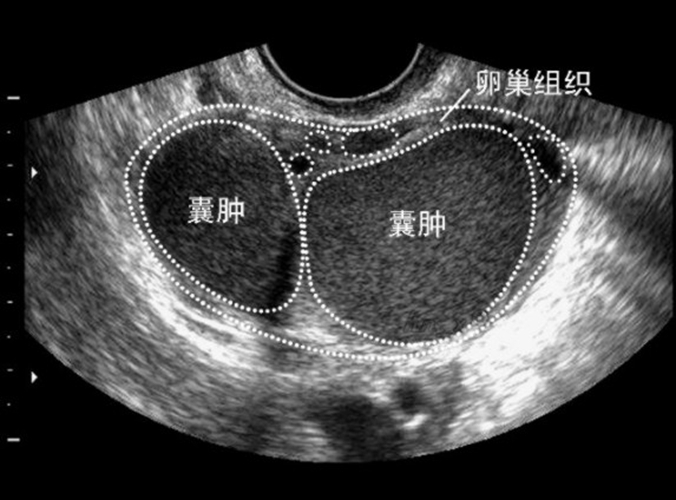

卵巢巧克力囊肿实际上是子宫内膜异位症的一种病变,其主要是在卵巢发生子宫内膜种植后逐渐形成的,一般巧克力囊肿从小而大,最大时能够增长到直径25厘米,轻者影响月经周期,重者导致不孕、危及患者生命。

(1)、影像学检查:阴道和腹部B型超声检查能够确定巧克力囊肿的位置、大小、形状和囊内容物。